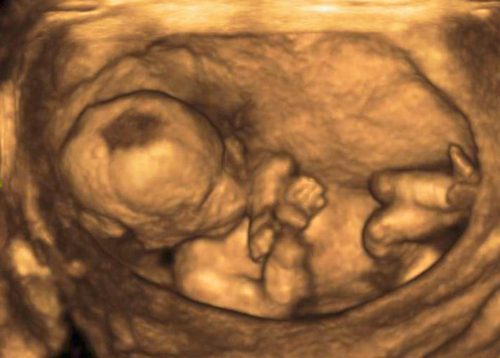

妊娠20週頃になると、胎児の大きさは17~23cm、体重は250~350gに成長します。エコー検査では顔の様子がだいぶわかるようになり、心臓や背骨も見えるようになります。手足が伸び、見た目は新生児とほとんど変わりませんよ。もう少し経つとエコーに全身が映らなくなるため、4Dエコーや3Dエコーで胎児の全体像を見たい場合は妊娠20週前後がおすすめです。

4Dエコーで顔がはっきりわかった!

妊娠20週3日に最初で最後の4Dエコーを撮ってもらいました。夫や息子たちも一緒に見られるよう、わざわざ週末に予約して行きました。

まず最初に思ったことは「4Dエコー、すごい!」ということです。顔までくっきり映り、息子たちにそっくりだということがわかりました。お腹の中にちゃんと人間が入っているんだと改めて感激しました。まだ脂肪がない分、目鼻立ちがくっきりしていて、とてもかわいかったですよ。

「多分女の子っぽいですね」と言われ、第3子にして初めての女の子だと家族全員が大興奮。しかしその後、妊娠10ヶ月の健診で男の子だと判明しました。